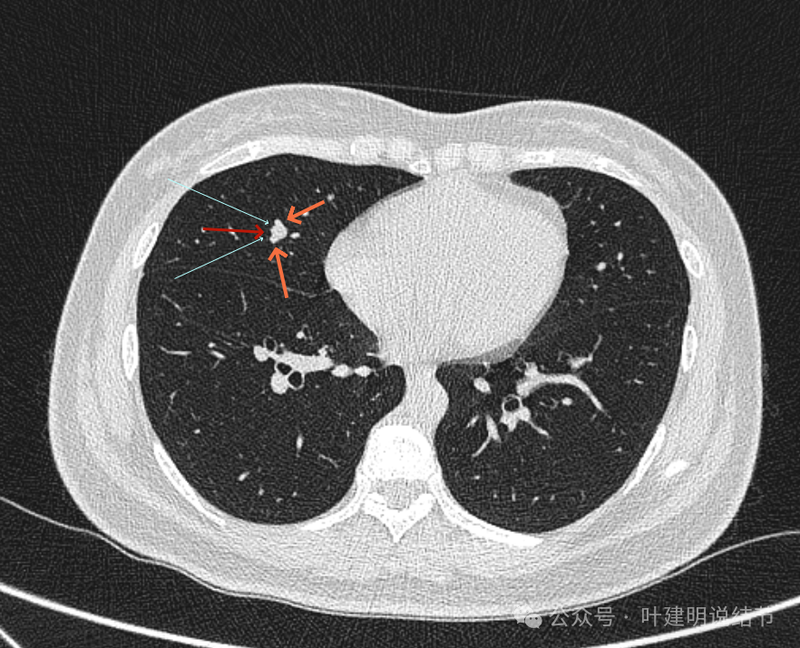

上图也示病灶与血管的关系。

上图像病灶位于中央,周围有三支不同血管围着它。

确实是三支血管围着病灶,中间的是结节,另三处均是血管。